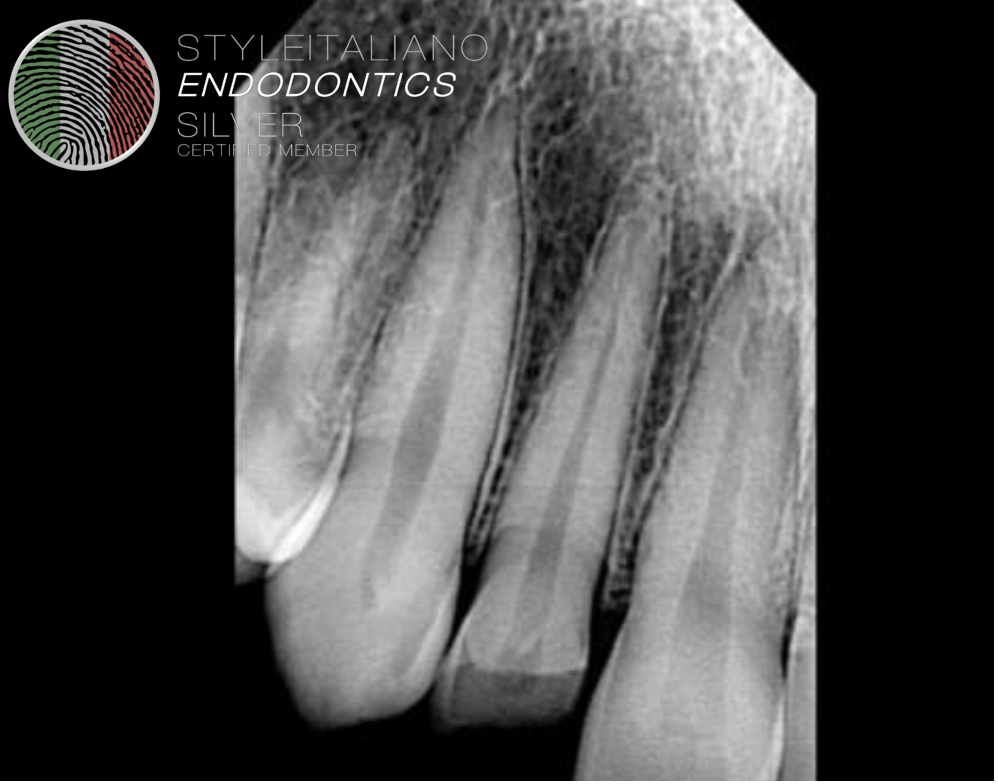

Fig. 4

Patient was not able to report on time. And root resorption was seen after 2 months time.